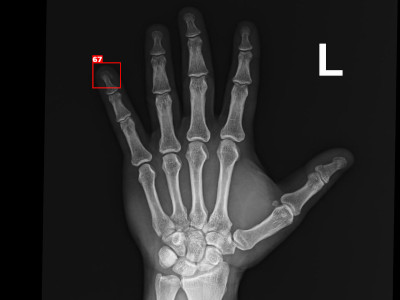

Detecção de fratura do quinto metarcapo em Raio X

Fratura do quinto metarcapo